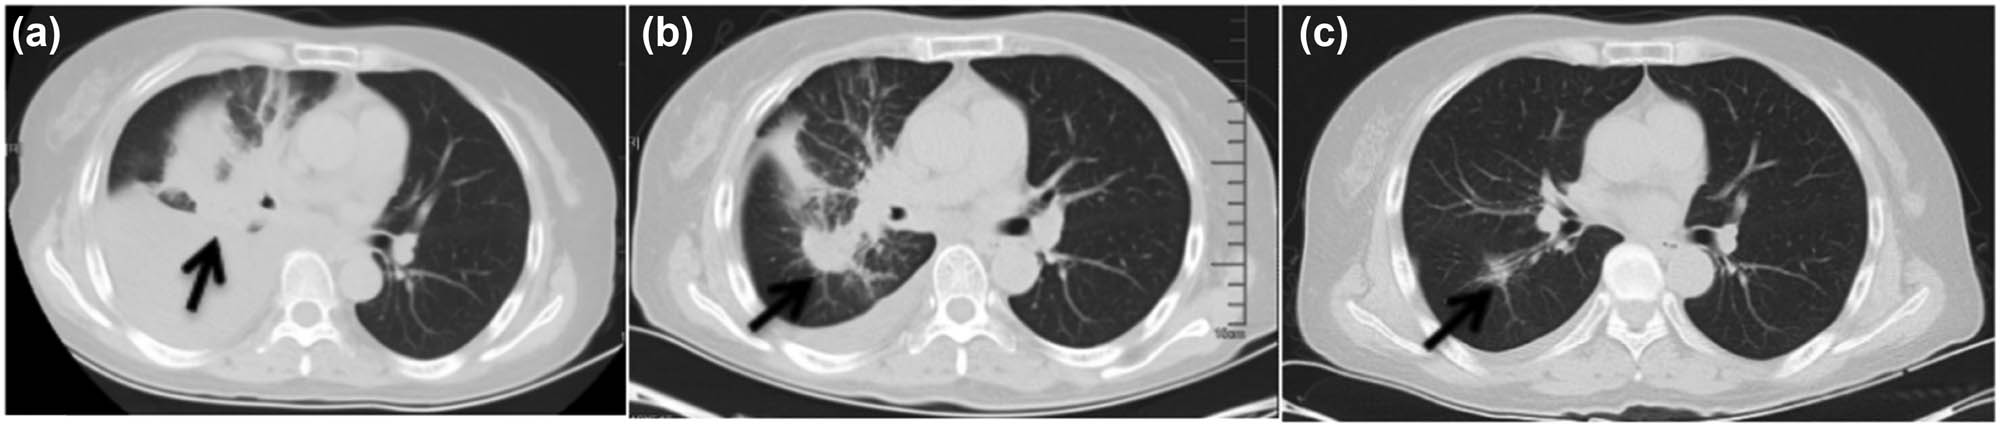

The 63-year-old female never-smoker was admitted to our department for the first time on December 23, 2015, due to cough and dyspnea for over 20 days. Her chest computed tomography (CT) showed space-occupying lesions in the right hilum and enlarged lymph nodes in the mediastinum, atelectasis of the right lung, massive pleural effusion in the right side, and multiple nodules in both lungs (Figure 1a). Magnetic resonance imaging (MRI) showed gadolinium-enhanced multiple abnormal intensification foci in the brain which were considered to be multiple metastatic tumors (Figure 2a, c, and e). The serum concentration of the carcinoembryonic antigen (CEA) was 18.75 ng/mL. Right thoracic closed drainage and pleural biopsy were performed, resulting in a total of 1,500 mL yellow pleural fluid drained out (Figure 1b) and a pleural fluid CEA of 17.55 ng/mL.

Chest CT. The arrow points to the tumor site. (a) At initial diagnosis, (b) after closed drainage of the right chest, and (c) after targeted therapy of gefitinib.

The patient received gefitinib and intermittent zoledronic acid for bone metastases until 20 months, and then MRI showed that BMs which had disappeared and shrunk (Figure 2b and d) after gefitinib were progressing again. The cancer lesions in lungs of the patient were significantly reduced (Figure 1c) after gefitinib and did not progress during the treatment period. Systemic bone imaging showed that the metabolic activity of hypermetabolic lesions in the middle part of the left femur was significantly decreased after gefitinib treatment (Figure 4b) and the patient had never been affected by lower limb discomfort.